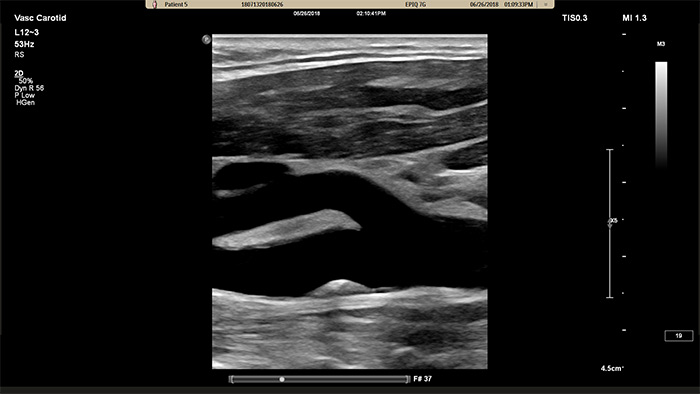

XL14-3 xMATRIXトランスジューサは、実に56,000素子を配列し、すべて別のマイクロチャネルに接続されています。XL14-3トランスジューサは、血管構造およびプラーク形態を描出するための薄いスライスと多段フォーカス機能を備えています。主なメリットは、狭窄や不安定プラークを評価する際の診断確度の向上があります。

XL14-3 xMATRIXトランスジューサは、縦断面および横断面を同時にリアルタイムで描出して血管検査の標準アプローチを超える、xPlaneイメージングを提供します。xPlaneイメージングの主なメリットとして、トランスジューサを回転することなく直交断面を収集できる点が挙げられます。トラックボールのシンプルな動きで、完全な解剖学的評価を提供し、検査時間を短縮できます。